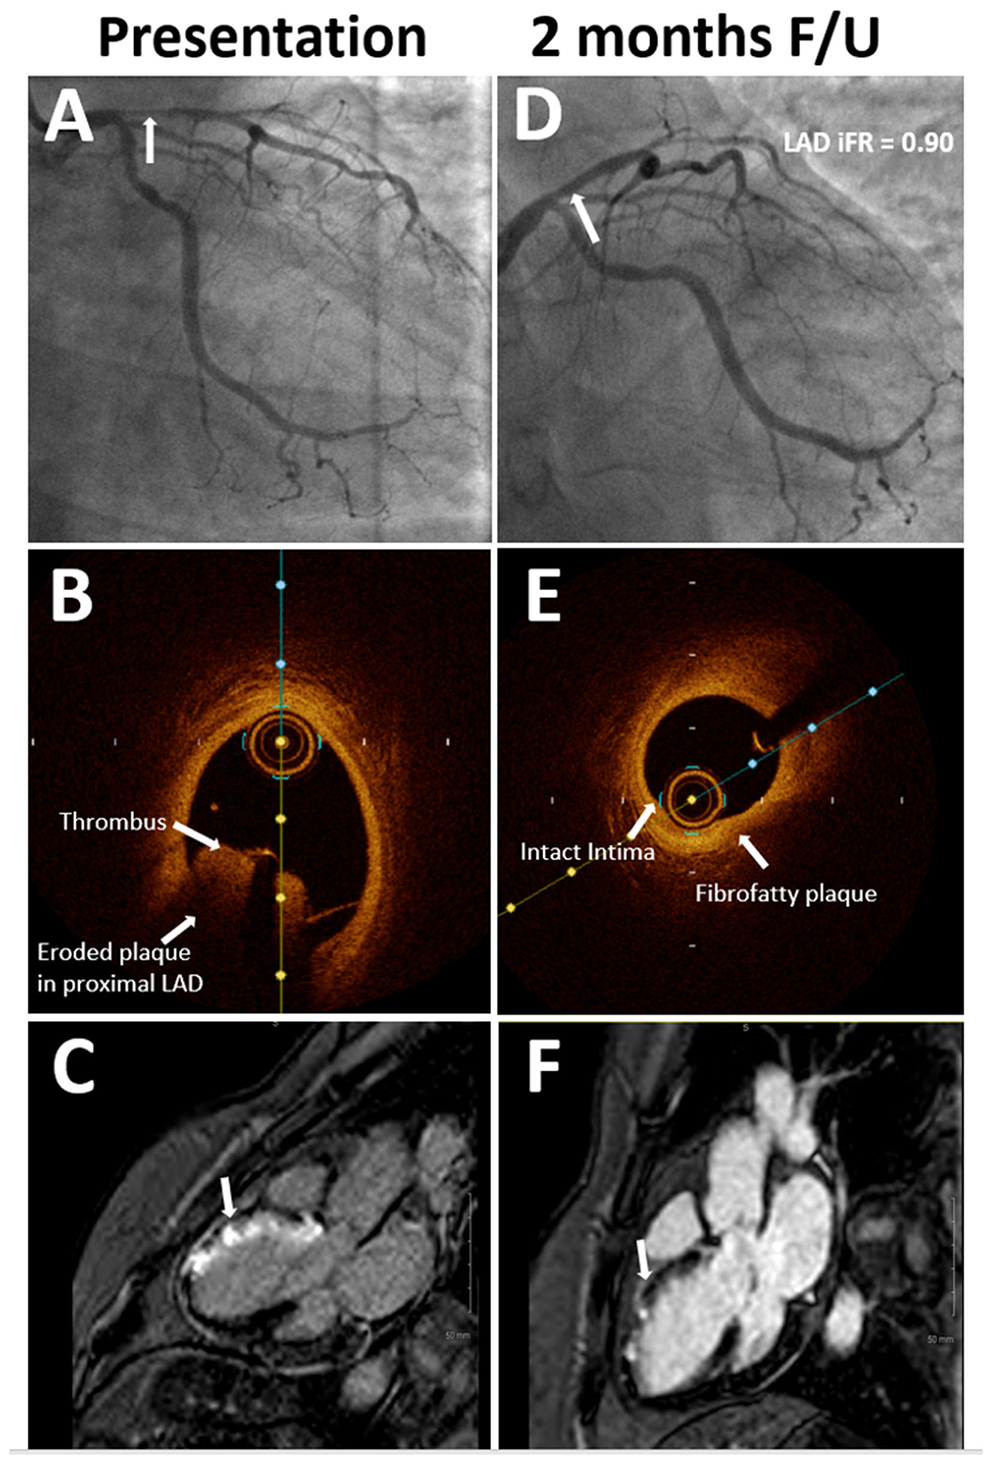

Figure 2

(A) Coronary angiography at presentation showing 80% stenosis (arrow) in proximal left anterior descending (LAD) with TIMI flow grade 2. (B) Optical coherence tomography (OCT) imaging at presentation showing significant thrombotic burden (arrow) and eroded plaque in the LAD. (C) Late gadolinium enhancement on cardiac magnetic resonance (CMR) imaging at presentation (arrow) consistent with LAD territory infarct. (D) Coronary angiography at 2-month follow-up showing non-obstructive stenosis (arrow) in proximal LAD. (E) OCT imaging at 2-month follow-up shows stable plaque in proximal LAD. (F) Non-transmural infarct was seen on the follow-up CMR imaging, which was done 6 weeks after the first presentation.

The patient was loaded with aspirin and ticagrelor, and emergently taken to the cardiac catheterization lab. Coronary angiography showed acute thrombotic occlusion of the proximal left anterior descending artery (LAD) with spontaneous recanalization and 80% stenosis, with thrombolysis in myocardial infarction (TIMI) flow grade 2 distally (Figure 2A). Given the significant thrombus burden, we proceeded with aspiration thrombectomy which established TIMI flow grade 3. Following thrombectomy, optical coherence tomography (OCT) of the LAD was performed to evaluate the underlying etiology for the acute coronary event. OCT revealed a significant residual thrombotic burden overlying an eroded, non-obstructive plaque (Figure 2B). After additional rounds of thrombectomy, repeat OCT showed plaque erosion with no evidence of plaque rupture. A final coronary angiography revealed 50% residual stenosis. Stenting was deferred, given the non-obstructive nature of the underlying plaque, absence of plaque rupture, restoration of TIMI flow grade 3, and improvement of symptoms and resolution of the ST elevation on ECG (Electrocardiogram). An Eptifibatide bolus of 180 mcg/kg was administered, followed by a 2 mcg/kg/min infusion for 18 h. On day 3 of admission, cardiac MRI (CMR) showed a left ventricular ejection fraction (LVEF) of 50% and myocardial changes consistent with the subacute stage of medium-sized infarction in the LAD territory. Specifically, we noted late gadolinium enhancement involving the basal to mid anteroseptal, distal septal, and distal anterior walls, consistent with a transmural infarction (Figure 2C). The patient was discharged on dual antiplatelet therapy and high-intensity statin (atorvastatin 80 mg daily). Smoking cessation counseling was done, nicotine patches were prescribed, and the patient was enrolled for cardiac rehabilitation therapy.

At 2 months follow-up, the patient was asymptomatic. Repeat angiogram showed a non-obstructive lesion in the proximal LAD (Figure 2D). Functional assessment with instantaneous wave-free ratio (iFR) confirmed that the intermediate stenosis was not hemodynamically significant (iFR=0.90). OCT showed a stable, non-obstructive, thick cap fibro-fatty plaque in the proximal LAD with no evidence of thrombus (Figure 2E). Repeat CMR showed remarkable recovery with improvement in the LVEF to 58% and the late gadolinium enhancement pattern was now consistent with a non-transmural infarction of the mid anteroseptal (50% involvement), distal anterior, and distal septal segments (50–75% involvement) (Figure 2F). Her low-density lipoprotein at the time of presentation was 79 mg/dl which improved to 54 mg/dl on a high-intensity statin. On her most recent follow-up, 27 months after the initial presentation, she continued to do well. She had successfully quit tobacco with counseling and temporary nicotine replacement therapy, and her last cigarette use was on the day of her myocardial infarction (Table 1). We plan to continue to treat her with dual antiplatelet therapy for as long as she can tolerate it without bleeding issues and consider anatomic or functional assessment (preferably a non-invasive study with coronary computed tomography angiography (CCTA) or stress testing) only if she were to have symptoms concerning for angina.